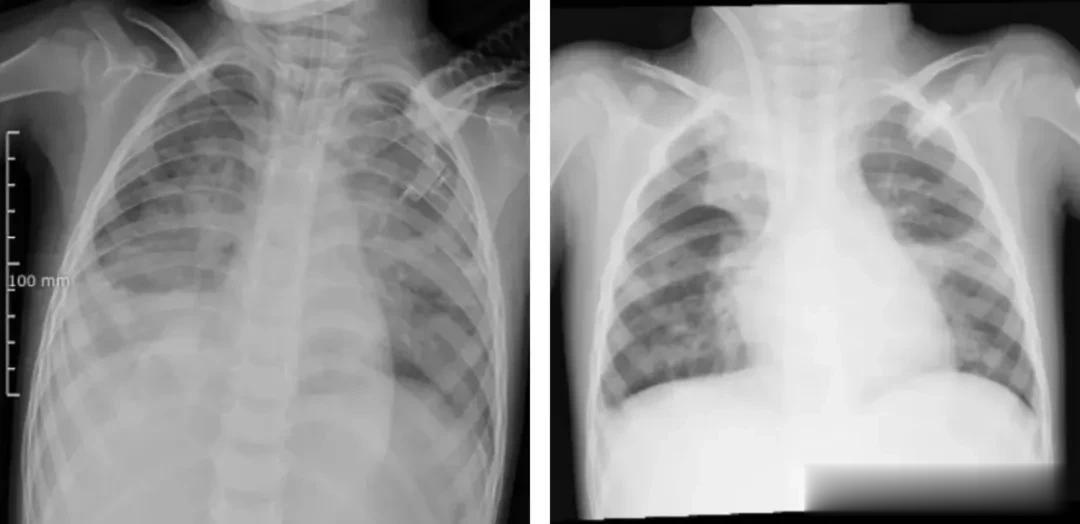

(左图为ECMO上机前,肺部结构模糊,呈现“白肺”影像表现。右图为ECMO支持治疗5天后,肺部影像清晰度明显改善)